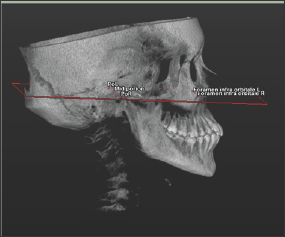

Figure 1: The fixed plane passing through between the lowest point of the right and left infraorbital foramen with the porion.

For this study, 100 patients were enrolled who had been referred to the Eskisehir Osmangazi University Faculty of Dentistry in Turkey and required a Cone Beam Computed Tomography (CBCT) examination as part of their routine examination. The CBCT images were obtained in a standing position using the CBCT machine (Planmeca Promax 3D mid, Helsinki, Finland). The exclusion criteria were craniofacial syndrome, presence of a cleft lip or palate, and impacted teeth. On the 3D images of the CBCT data in Digital Imaging and Communications in Medicine (DICOM) format, a fixed plane passing through the lowest point of the right and left infraorbital foramen with the porion was created using Simplant O&O dental software (Materialise, Leuven, Belgium) (Figure 1). The determined points were placed by checking the root apexes of the bilateral maxillary canine, premolar, and molar teeth on all three planes (axial, coronal, and sagittal). In multi-rooted teeth, the longest root was taken as reference (Figure 2).